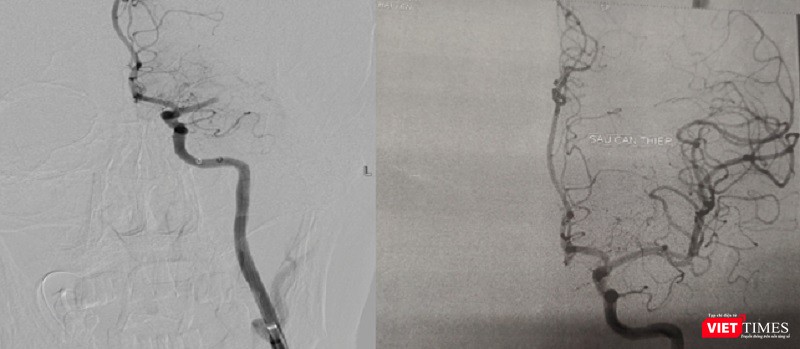

![]() |

| Hình ảnh động mạch não trước và sau khi hút huyết khối |

Ngay lập tức, hai cuộc phẫu thuật được thực hiện cùng lúc để cấp cứu bệnh nhân. Hai ekíp bác sĩ can thiệp thần kinh và can thiệp mạch vành nhanh chóng thống nhất phương án xử lý và quyết định thứ tự các kíp can thiệp, bắt đầu hút huyết khối để tái thông dòng chảy trên hệ mạch máu não trước, sau đó tiến hành can thiệp đặt stent động mạch vành cho bệnh nhân.